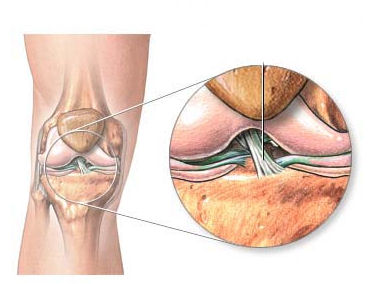

Einfache anatomische Darstellung des vorderen Kreuzbandes

Sie sind der Zentralpfeiler des Knies und laufen gekreuzt durchs Gelenk. Gemeinsam mit den Menisken, den Seitenbändern und der umgebenden Muskulatur stabilisieren sie das Kniegelenk. Diese Gelenkskonstruktion erlaubt das sogenannte "Rollgleiten" des Kniegelenkes. Nur so ist Skifahren, Fußball, Squash, Tennis und die Ausübung vieler anderer, uns liebgewonnener kniebelastender Sportarten möglich. Pro Knie gibt es ein vorderes und ein hinteres Kreuzband. Hauptsächlich betroffen im Ski- und Fußballsport ist das vordere Kreuzband. Beim Riss des vorderen Kreuzbandes handelt es sich um eine schwere, das Kniegelenk betreffende Verletzung, die meistens mit starken Schmerzen einhergeht.